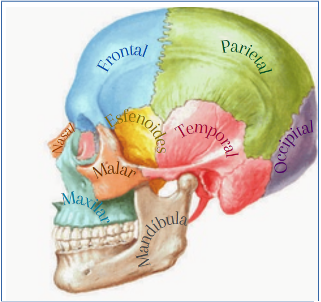

– Craneal. La osteopatía craneal es una técnica suave que trabaja el sistema nervioso central. Esta modalidad de osteopatía la aplicamos en tensiones emocionales, estrés, migrañas, vértigos, así como para terminar de eliminar lesiones articulares como pueden ser de sacro, lumbares, escoliosis…